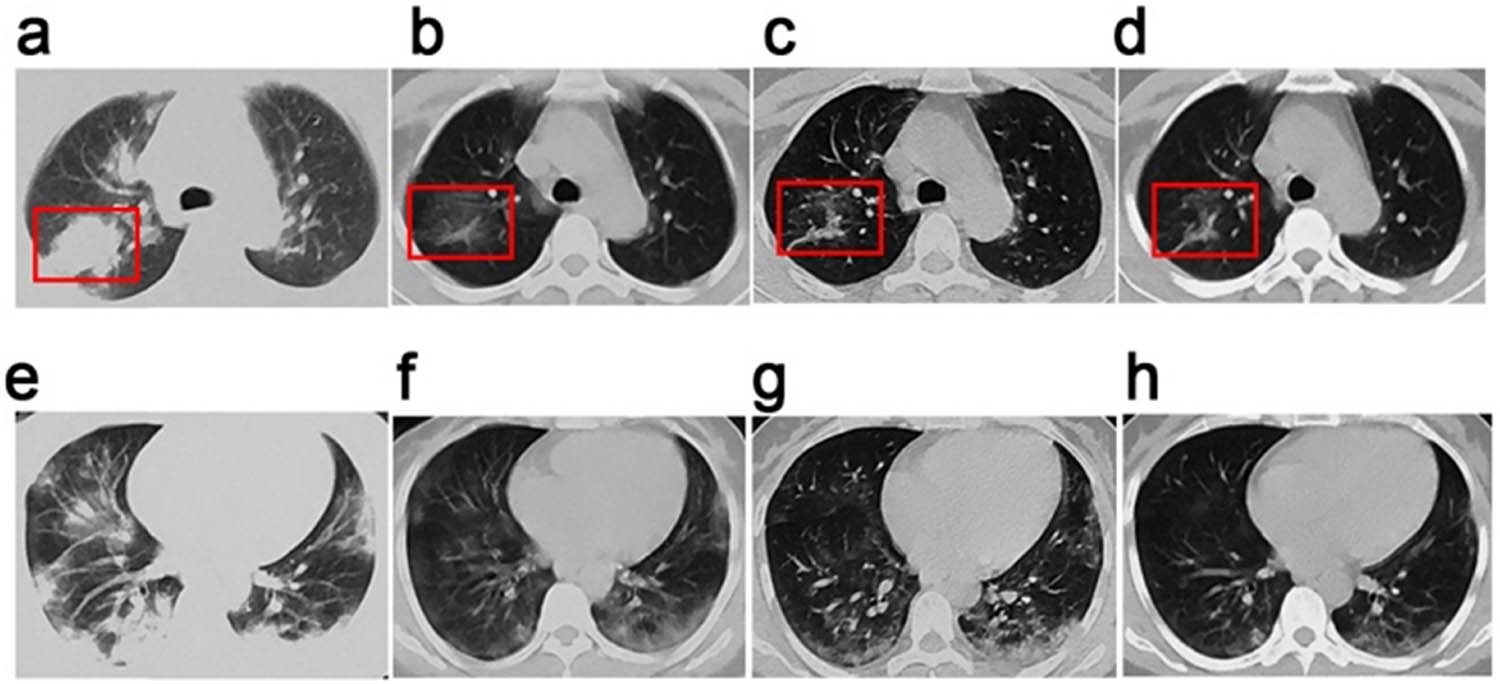

A 41-year-old woman travelled from Wuhan, Hubei province, China, to Changchun, Jilin province, on 19 January 2020. She attended the fever clinic of Changchun Infectious Diseases Hospital on the afternoon of 19 January, presenting with an intermittent fever (highest temperature 38.2°C) and cough, chest tightness, and fatigue that had persisted for 8 days. She was admitted to hospital the following afternoon after throat swab specimens collected from the upper respiratory tract tested positive for SARS-CoV-2 nucleic acid by RT-PCR (reverse-transcriptase polymerase chain reaction) [3,19]. She presented results of laboratory tests performed at Tongji Hospital in Wuhan on 17 January: lymphocyte count (low): 0.89 × 109/L, neutrophils: 80.4%, serum CRP (C-reactive protein): 164.7 mg/L. Relevant multifunctional monitoring indicators on admission in our hospital were: transcutaneous oxygen saturation (SpO2): 93%, temperature: 37.4°C, respiratory rate: 20 breaths/min, pulse: 80 beats/min, blood pressure: 126/76 mm Hg. Auscultation of both lungs was unremarkable. Chest computed tomography (CT) showed consolidation in the right lung and peripheral ground-glass opacities in both lungs (Figure 1a and e). Her underlying health was good, and she had no known comorbidities. In line with relevant national guidelines in force at the time [20], she was diagnosed as a severe COVID-19 case and treated accordingly.

Chest CT images of a 41-year-old woman with SARS-CoV-2 infection. Chest CT images for a 41-year-old woman who presented at Changchun Infectious Diseases Hospital with fever and cough. (a–d) Images showing lesions in the posterior segment of the inferior lobe of the right lung. (a) Image taken at admission before the onset of treatment showing consolidated opacities in the right lung. (b and c) Images obtained on days 4 and 7 showing marked absorption of pulmonary consolidations. (d) Image taken on day 10 showing stripe-like opacities indicating recovery of the lung from infection. (e–h) Images of the lower lobe of the lung taken, (e), at the onset of treatment, (f), on day 4, (g), on day 7, and (h), on day 10, showing the infection and progressive treatment efficacy. Ground-glass opacities in the pulmonary pleural can be seen to reduce in the lower lobe of the lung from (e) to (h).

Moxifloxacin (0.4 g, IV, od) was used to prevent secondary infections, methylprednisone (40 mg, IV, od) was used to decrease inflammatory exudates in the lungs, acetylcysteine (0.2 g, po, tid) was given to prevent lung fibrosis, and lopinavir–ritonavir (2 × 200 mg/50 mg, po, tid) was used as an antiviral treatment. A chest CT scan performed on day 4 was compared to that taken at admission to assess treatment efficacy (Figure 1a, b, e, and f); evidence suggested absorption of pulmonary lesions in both lungs and of the inflammatory consolidation in the right lung. The patient’s temperature had returned to normal, and her cough, chest tightness, and fatigue were alleviated to some extent. Transcutaneous oxygen saturation (SpO2) increased to 97%. Laboratory tests were performed as required, beginning the morning after admission to hospital (HD2; Table 1).

Lopinavir–ritonavir treatment was discontinued because of the improvements observed above, and the dosage of intravenous acetylcysteine was adjusted to 50%. Other elements of the treatment described above were maintained. Comparison of chest CTs taken at the end of Phases I and II indicated further improvement, with ongoing absorption of pulmonary lesions (Figure 1b, c, f, and g).

Methylprednisone was replaced with prednisone because of the improvements observed, and the dosage was adjusted to 20 mg (IV, od). Comparison of chest CT scans from the end of phases II and III once again indicated steady absorption of pulmonary lesions in both lungs (Figure 1c, d, g, and h). By this point, the patient felt significantly recovered, and her cough, chest tightness, and fatigue were almost gone. Lymphocyte and CRP levels also returned to normal (Table 1). RT-PCR tests for SARS-CoV-2 nucleic acid were conducted on days 9 (27 January) and 11 (29 January) of hospitalization. Both tests returned negative results and the patient was discharged from hospital on completion of treatment on 30 January.